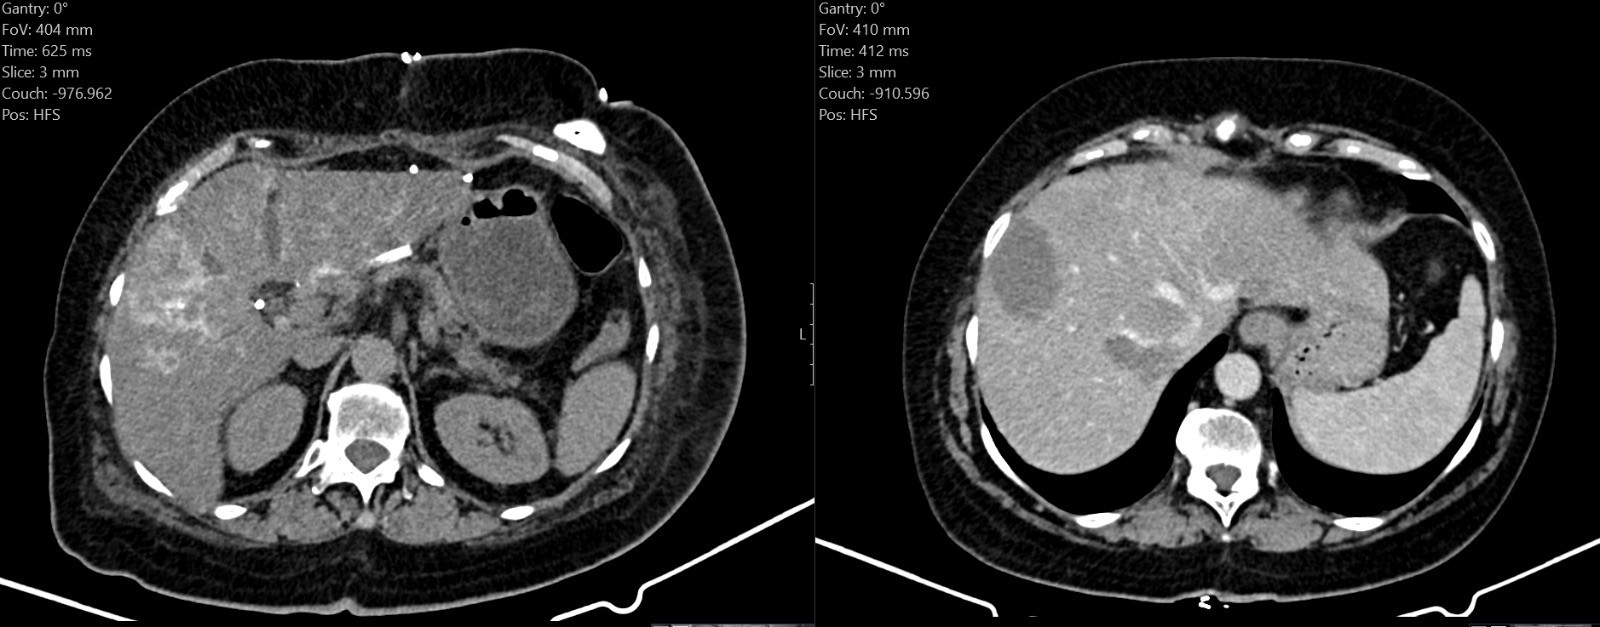

In a notable step in Cancer Care in Palestine, the Surgical Department at Augusta Victoria Hospital has introduced a new technique for treating metastatic liver tumors that are inoperable, enabling direct delivery of chemotherapy to the tumor.

Dr. Marwan Abu Farah and Dr. Mohammed Adele, surgeons at Augusta Victoria Hospital, emphasized, "In cases where colon cancer has metastasized to the liver, this technique, which delivers treatment directly to the tumor, may enhance its response rate and thus the possibility of surgical removal."